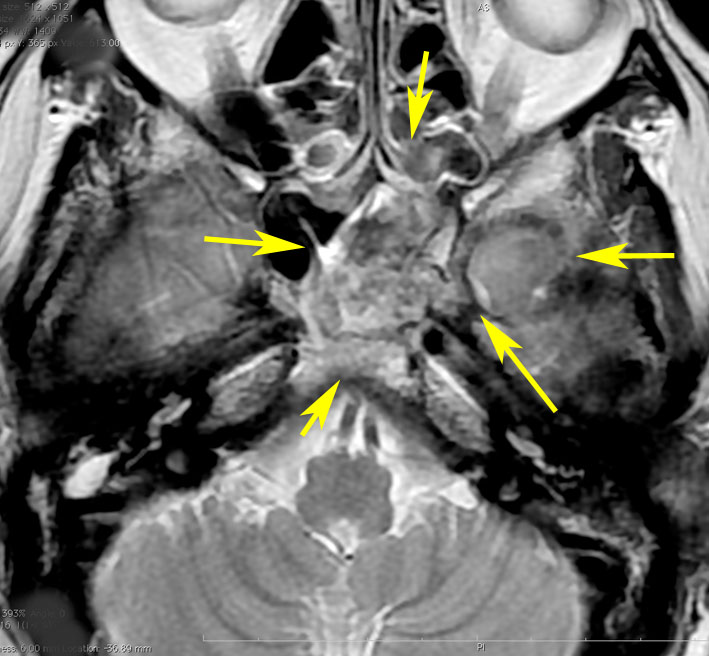

CTでは,斜台から左蝶形骨にかけて不規則な骨破壊像がみられます。

MRI T2強調画像(左)では等信号から高信号のまだらな境界が不明瞭な腫瘍が斜台から左海綿静脈洞内に浸潤しているのがみられます。T1強調ガドリニウム増強では,腫瘍がまだらに増強されています。トルコ鞍から鞍上部に伸び,視交差を侵し第3脳室底まで伸展しています。脊索腫が硬膜内に浸潤して神経組織と癒着することは珍しいことではありません。